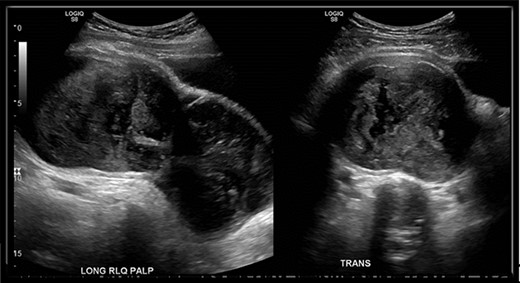

An abdominal ultrasound (US) was performed and showed a hypo-vascular mass in the right hypogastric region (Fig. 1). Abdomen and pelvis computed tomography (CT) scan with intravenous contrast identified a large complex mass (19.3 × 8.7 × 13.5 cm) with a partially calcified soft tissue rim with some internal calcifications. The mass extended from the central pelvis to the right lower quadrant of the abdomen (Fig. 2). The mass appeared to be attached to the cecum and no normal appendix was identifiable on imaging. There was no free fluid or evidence of metastasis. The tumor was compressing the bladder and sigmoid colon on CT scan, which explains the patient’s urinary and bowel symptoms.

US of right lower quadrant visualizing the hypo-vascular abdominal mass longitudinally and transversely; mass measured 18.5 × 8.1 × 11 cm in the right hypogastric region with only a small amount of visible internal flow on color Doppler.